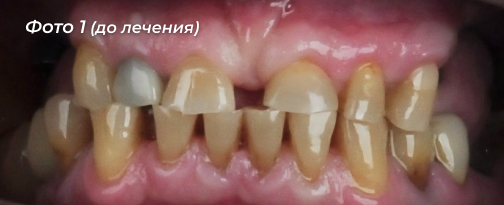

Проблема:  у пациента отсутствовали жевательные зубы, было выраженное снижение прикуса. Пациент отмечал трудности с пережёвыванием пищи, быструю утомляемость челюстей и недовольство внешним видом улыбки (Фото 1, 2).